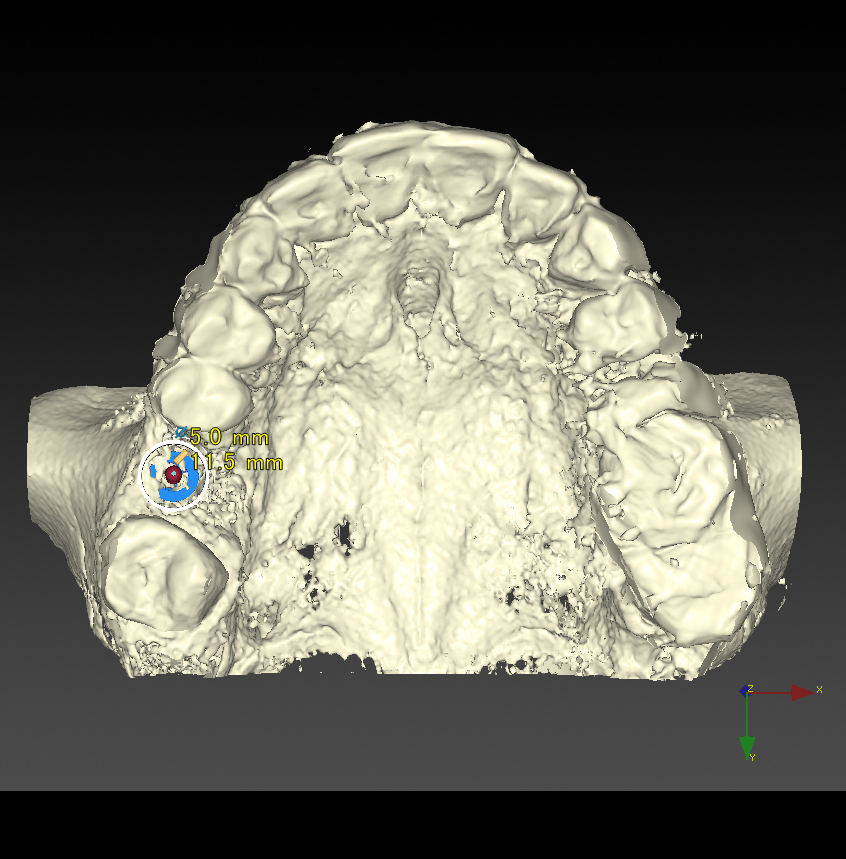

CT撮影で立体的な顎の骨を確認できます。

CTシミュレーション

CTデータをインプラント解析ソフトに入れ、手術のシミュレーションをします。

・骨の状態を確認し、骨造成が必要か見極めます。

・シミュレーションでインプラントが可能か確認し、インプラントのサイズを調べます。

CT撮影

埋入位置を決めるための装置(ラジオグラフィックガイド)を口腔内に入れCTを撮影します。

【ラジオグラフィックガイド】

埋入ガイド

CT画像上にて決定した埋入位置で製作された埋入ガイド。正確でスムーズな手術を行えます。

【埋入ガイド】